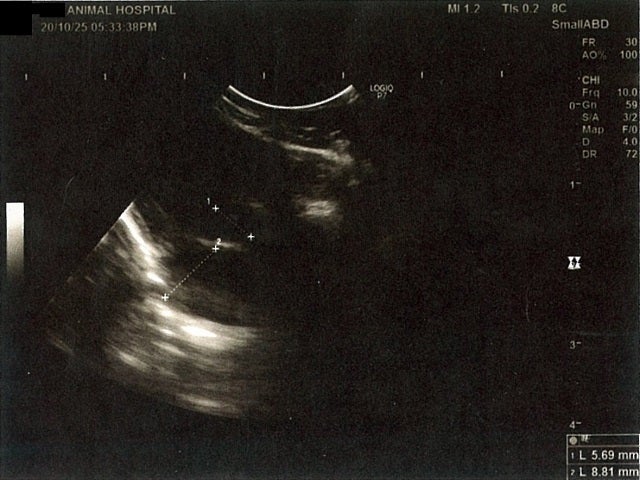

《心臓周りの胸部以外の全ての腹部で腹水がみられるとの診断です》

大網という部分で内臓を包む膜のようなものです。その周りに腹水が溜まっています。

膀胱周りに腹水が確認できるエコー写真